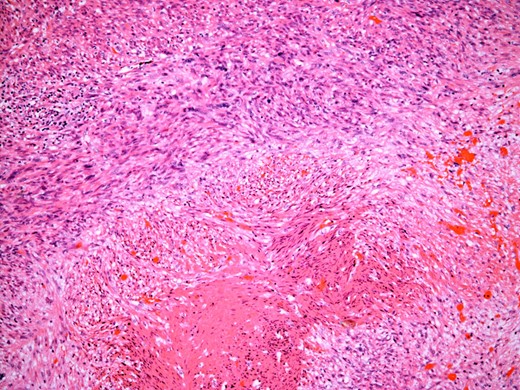

At the time of referral, the lesion had dramatically increased in size and become more symptomatic, therefore surgical excision was agreed. He underwent a trans-scrotal right epididymectomy where an irregular white mass measuring 15 × 46 × 35 mm3 was excised. Histological examination demonstrated a well delineated mass comprising fascicles of cytologically malignant spindle cells (Fig. 2). These showed moderate to nuclear pleomorphism, frequent mitotic figures, including atypical forms, and zones of coagulative necrosis (Fig. 3). Immunohistochemistry showed the tumour cells were strongly and diffusely positive for desmin, smooth muscle actin and h-caldesmon. FISH analysis for MDM2 amplification excluded a dedifferentiated liposarcoma, the main differential diagnosis at this site. Overall, the features were those of a paratesticular LMS, which was FNCLCC/Trojani grade 2.

The tumour comprises fascicles of atypical spindle cells showing prominent cytological atypia and nuclear pleomorphism. Zones of coagulative tumour cell necrosis are present.